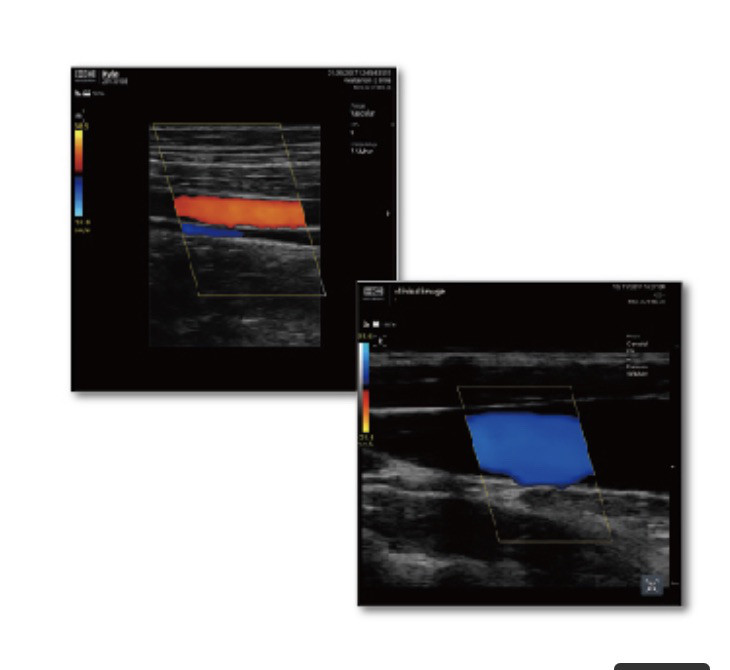

本日はこのような症状の患者さんがいたので紹介したと思います。

1ヶ月前からぎっくり腰になって、左のおしり〜左足首にかけて痛みが出ている方が来院されました。

前屈や腰を腰を反ると痛い。

歩いていると脚に痛みが出てくる(脊柱管狭窄症に特有な間欠性破行という症状)。

などの症状があります。

問診では坐骨神経領域の脊柱管狭窄症やヘルニアを疑います。

坐骨神経に対する各テストを行います。

SLRという坐骨神経を伸張させて痛みを誘発させるテストを行いました。

右は陰性、左は陽性でした。

つまり右の神経は問題なく、左の神経は圧迫されて神経に何らかのトラブルがあると考えられます。

坐骨神経はL4〜S3レベルで狭窄を受けると症状が出ます。

どこで狭窄を受けているが問題になります。

それは脊柱管(背骨の中の神経)、神経根(神経が左右に分かれて出る出口)なのか、神経の近くを通る筋肉の影響なのか、姿勢などの問題で神経が圧迫されるのか確認する必要があります。

それぞれの箇所で神経を一時的に圧迫から解放するテストを行いどこが原因なのか判断していきます。

今回の方はぎっくり腰からの神経痛なので脊柱管内での圧迫を最初に考えましたが、テストをしてもあまりいい効果はえられませんでした。

次に神経の滑走(動きを)よくするテストを行ったところ神経痛は緩和されました。

ぎっくり腰により神経が軽く圧迫され、炎症も出ていたので軽度の癒着が起き神経の動きが低下し神経を伸張する動きで下肢痛が出ていたのではないかと推測されます。

施術後はSLR(神経を伸ばすテスト)後も下肢痛は消失し、痛みも出なくなりました。

神経の滑走をよくするセルフケアをお伝えして継続していただくようにお願いしました。

坐骨神経も改善することがありますのでなかなか治らない方がいれば一度お問い合わせください。